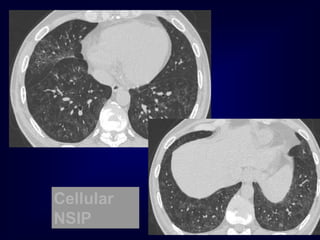

The Many ‘HRCT Faces’ of NSIP

Honeycombing not

a

prominent feature

!!!!

The Many ‘HRCTFaces’ of NSIP Honeycombing not a prominent feature !!!!